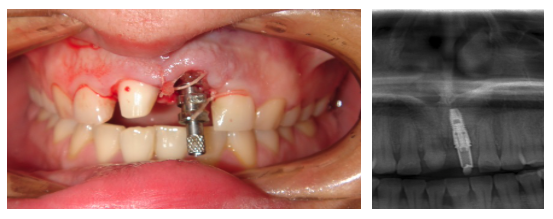

Rehabilitación del diente 21 con carga inmediata

Paciente con fractura de la raíz del diente 21. El caso se resolvió mediante exodoncia, implante inmediato y carga inmediata (diente fijo provisional en el día) e injerto de conectivo. La corona definitiva se confeccionó en metal cerámica .

Imagen de la toma de modelos de los provisionales en día de la cirugía de colocación del implante, y de la rx apical con el diente fijo provisional puesto